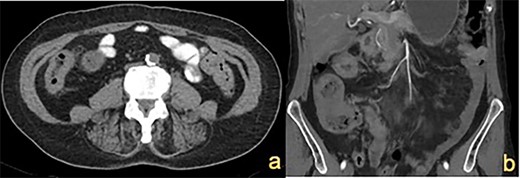

A 72-year-old female presented with abdominal pain and loss of weight. Computed tomography (CT) imaging demonstrated caecal and ascending colon thickening (Fig. 1a). Colonoscopy showed abnormal mucosa in the ascending colon that was unable to be traversed endoscopically (Fig. 2a) and slightly irregular mucosa at the hepatic flexure (Fig. 2b). The appearances were not typical of either a primary colon malignancy or a stricture secondary to inflammatory bowel disease (IBD). Biopsies were non-diagnostic, only showing mucosa with features of regeneration and repair. Given the patient was symptomatic, a laparoscopic right hemicolectomy was performed. Intraoperatively, a thickened firm ascending colon was seen suggesting possible submucosal involvement. Firm nodules were found in the terminal ileum mesentery and proximal transverse colon.

CT abdomen showing (a) thickened ascending colon wall and (b) thickened caecum and transverse colon (indicated by white arrows).

CT imaging showed a thickening in the right colon (Fig. 1b). Colonoscopy revealed a stricturing lesion in the hepatic flexure, with abnormal cobblestone-type mucosa without ulcerations or erosions, which transitioned to normal mucosa near the splenic flexure (Fig. 2c). Endoscopic appearances could have represented Crohn’s disease given the cobblestoning but appeared atypical. Biopsies were unable to prove malignancy or IBD but demonstrated fibrosis with features of prolapse or healed ischaemic damage. There were no oestrogen-positive cells.